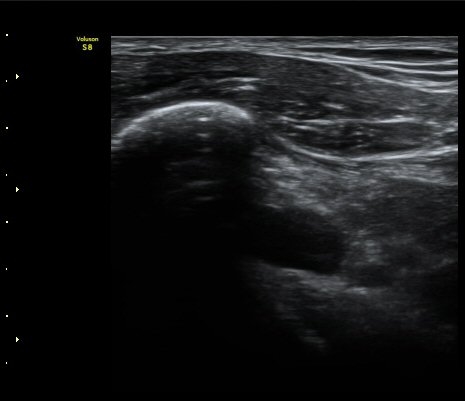

¿À±¸µ¹±â Ⱦ´Ü¸é°Ë»ç»ó ¿Áµ¹±â ¾Æ·¡, ³»Ãø, °ß°©ÇÏ±Ù°Ç Ç¥Ãþ¿¡¼­ ¼ö¾×Àú·ù°¡ °üÂûµÈ´Ù

(±×¸² 3, 4).